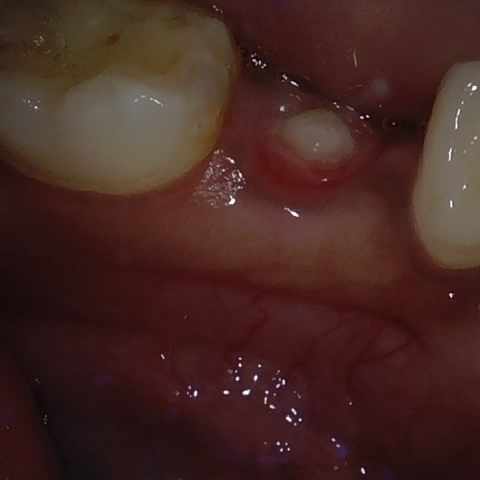

Annotated as "Good"